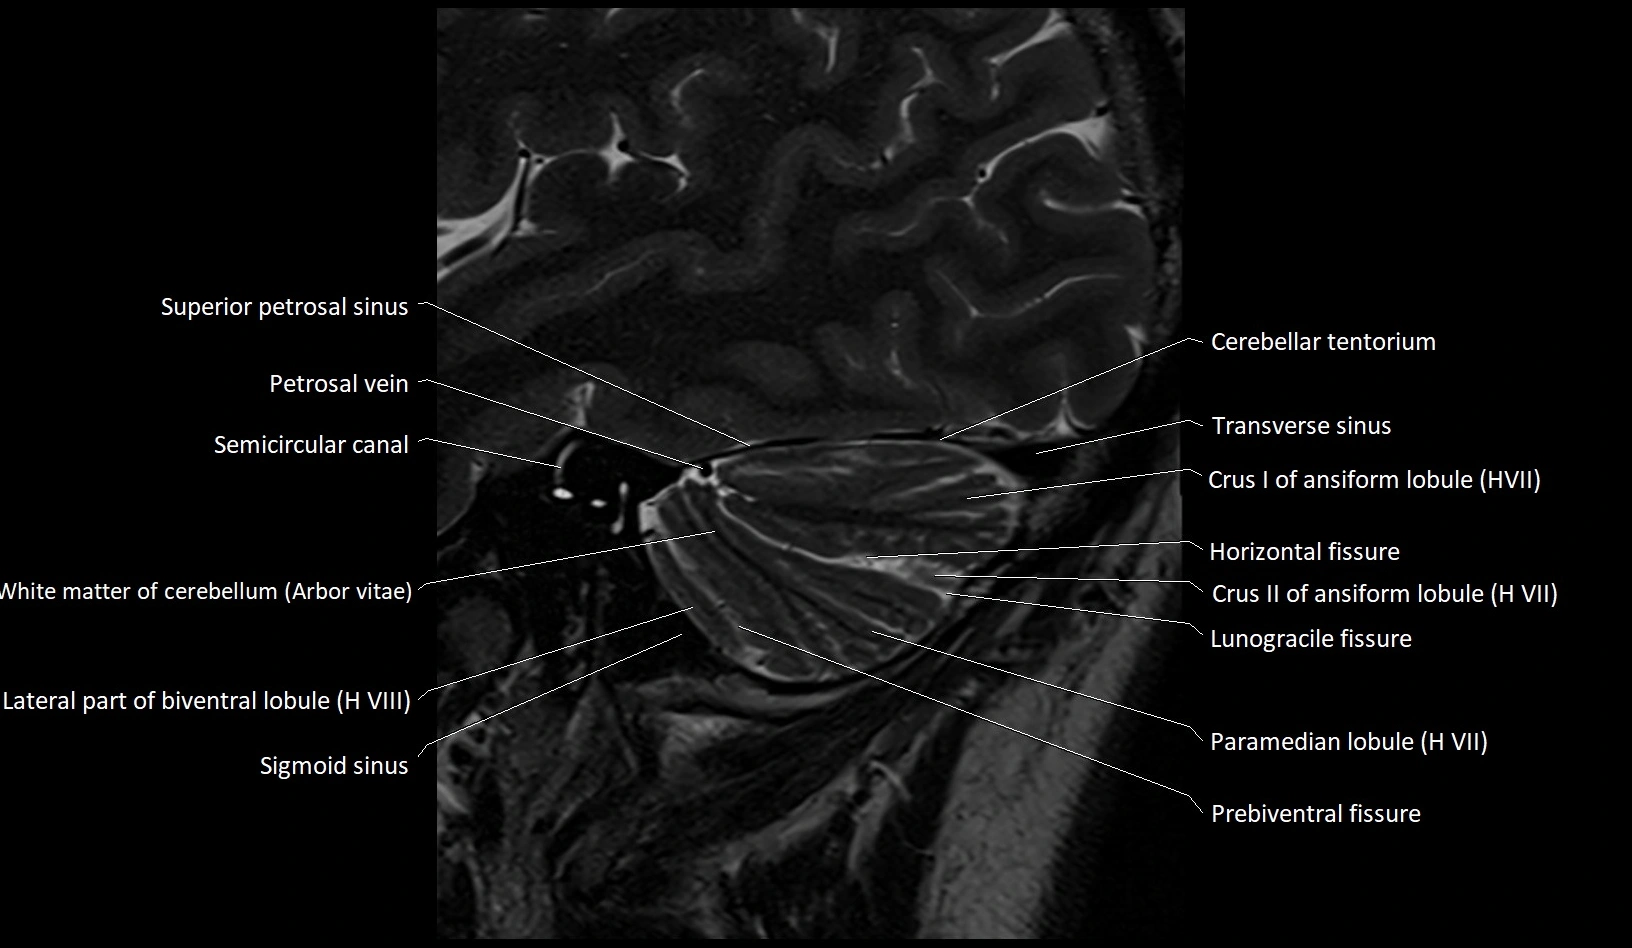

- Crus I of ansiform lobule of cerebellum

- Crus II of ansiform lobule of cerebellum

- Horizontal fissure (cerebellum)

- Lateral part of biventeral lobule

- Lunogracle fissure

- Lunogranicile fissure of cerebellum

- Paramedian lobule

- Paramedian lobule (HVII) of cerebellum

- Petrosal vein

- Prebiventral fissure

- Semicircular Canals

- Sigmoid sinus

- Simple lobule (HVI) of cerebellum

- Superior petrosal sinus

- Transverse sinus

- White matter of cerebellum (Arbor vitae)